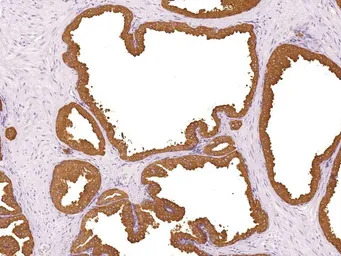

IHC-P analysis of human prostate tissue using GTX57196 Prostatic Acid Phosphatase antibody [IHC655]